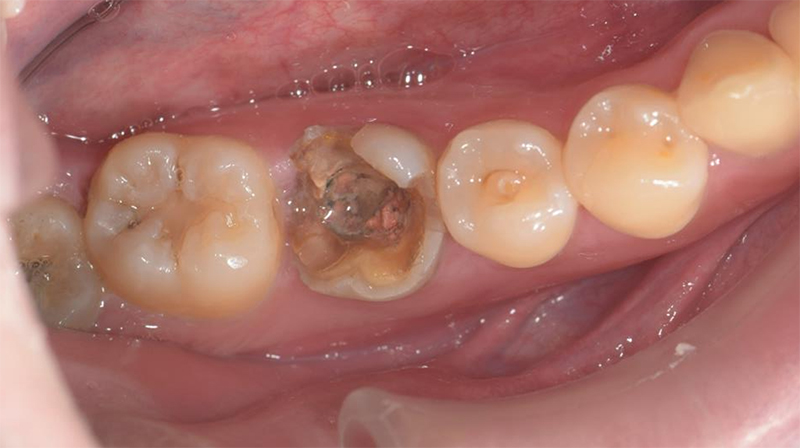

右下第一大臼齒斷裂

拔除右下第一大臼齒

術前